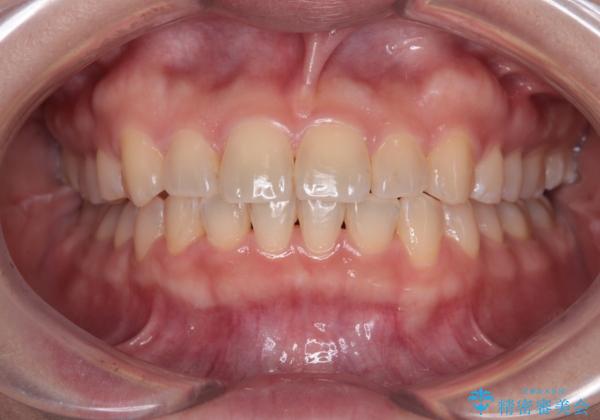

八重歯を治す 非抜歯のワイヤー矯正治療

- 左右の八重歯を気にして来院された患者様です。

ワイヤー装置でもマウスピースでも対応可能な歯列でしたが、マウスピース矯正は自己管理が煩わしいとのことでワイヤー矯正を選択されました。

八重歯である犬歯は歯根が長いため、上顎前歯が出っ歯になるリスクがあるため、必要に応じてアンカースクリューを用いて奥歯を後方に移動させる可能性をお伝えしました。

舌の突出癖により上下前歯が開咬となりましたが、舌のトレーニングと顎間ゴムの使用により、元々の被蓋関係に改善することができました。

アンカースクリューを用いて、出っ歯仕上がりを回避し、正中位置も改善することができました。